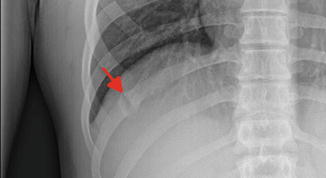

외상의 골절과는 다르게 여러개의 뼈가 부러지는 형태가 아닌 단일뼈가 부러지는 형태의

피로골절 형태의 골절이 생기는 경우가 많습니다.

진단은 물론 X-ray 나 CT, bone scan 같은 영상검사로 하게 되지만